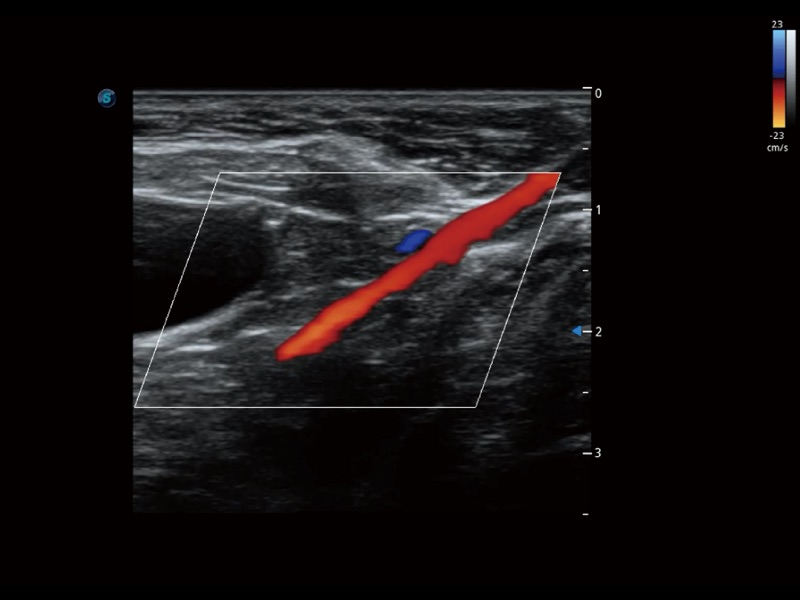

• 宽景成像

通过色彩血流和实时宽景相结合,可观察到完整的静脉或动脉的血流,方便医生检查。实时扫查过程中,如有任何操作失误也可以很容易地进行回扫擦除,而不会中断扫查。

(犬)髂动脉血流